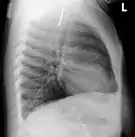

На рентгенограмме органов грудной полости (слева — в прямой, справа в боковой проекции) — видно инородное тело (монета) пищевода. | ||

Одна из распространённых локализаций инородных тел — желудочно-кишечный тракт. Возможные пути проникновения инородных тел — ротовая полость[13] или прямая кишка[14]. Дети чаще проглатывают монеты[15], у взрослых в 75% случаев инородными телами служили мясные кости[16].

Наиболее часто проглоченные предметы обнаруживают в пищеводе или желудке, реже в глотке или двенадцатиперстной кишке[17].